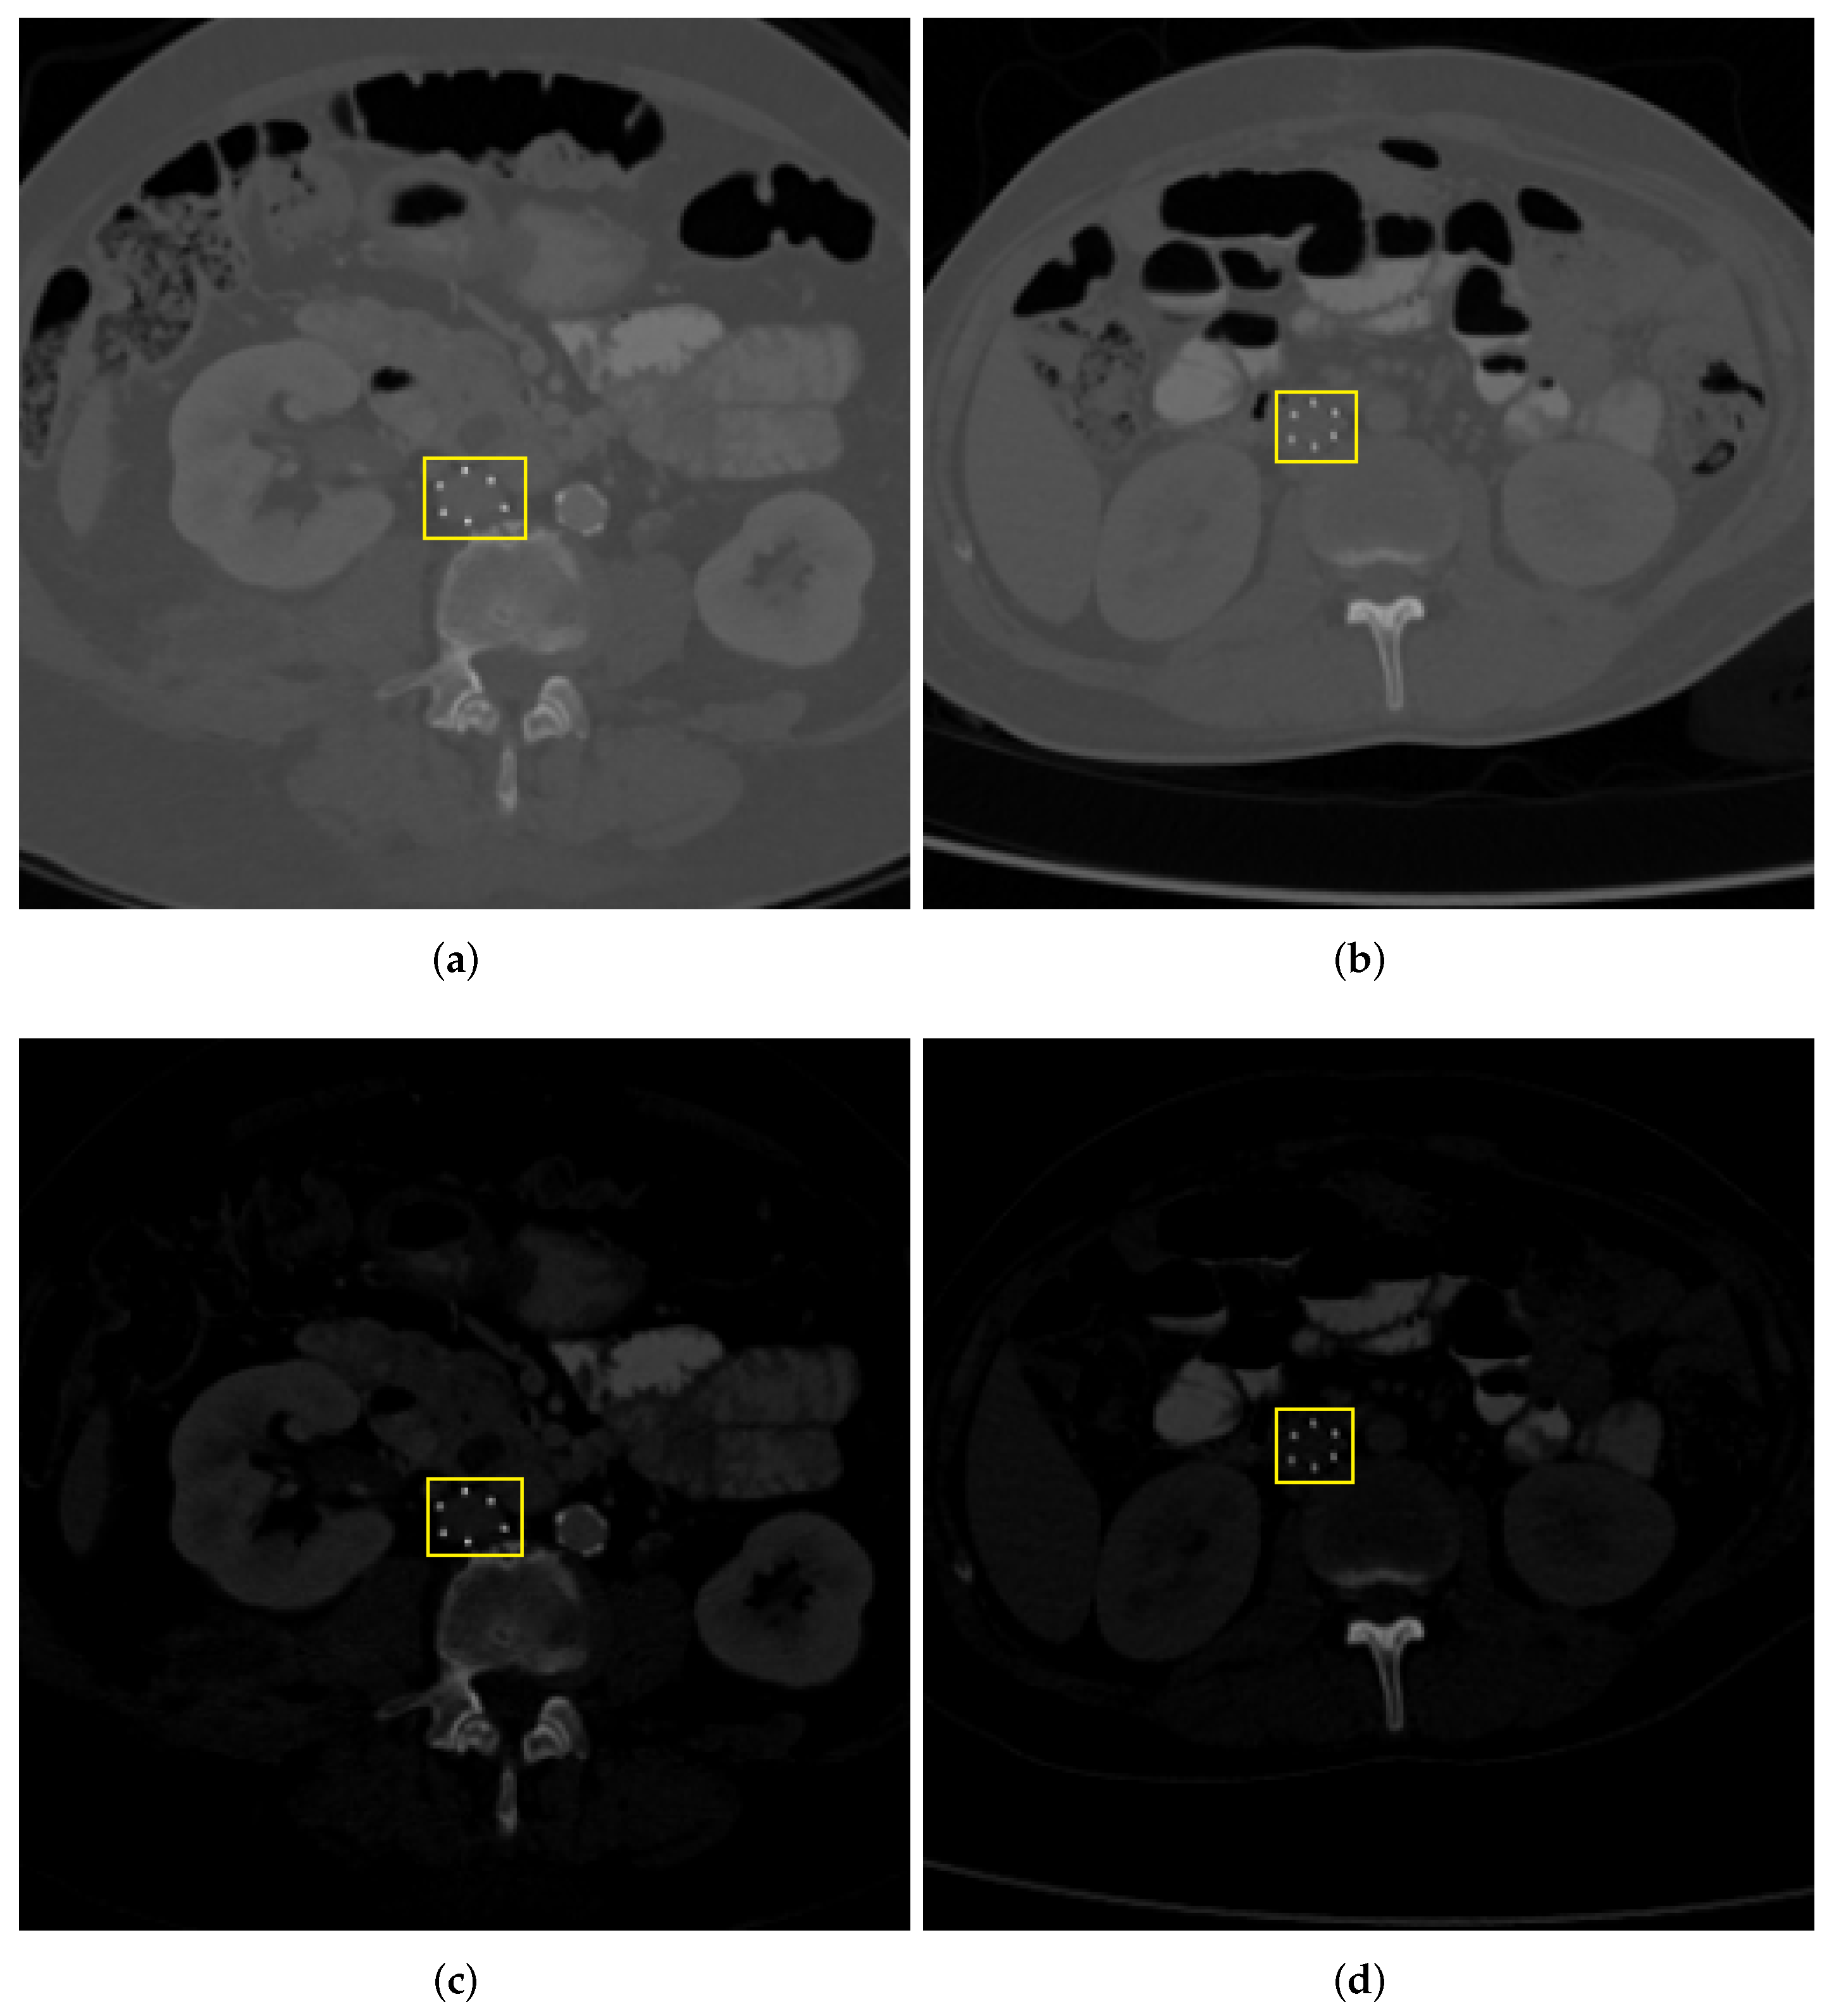

3.2. Spatial Cropping